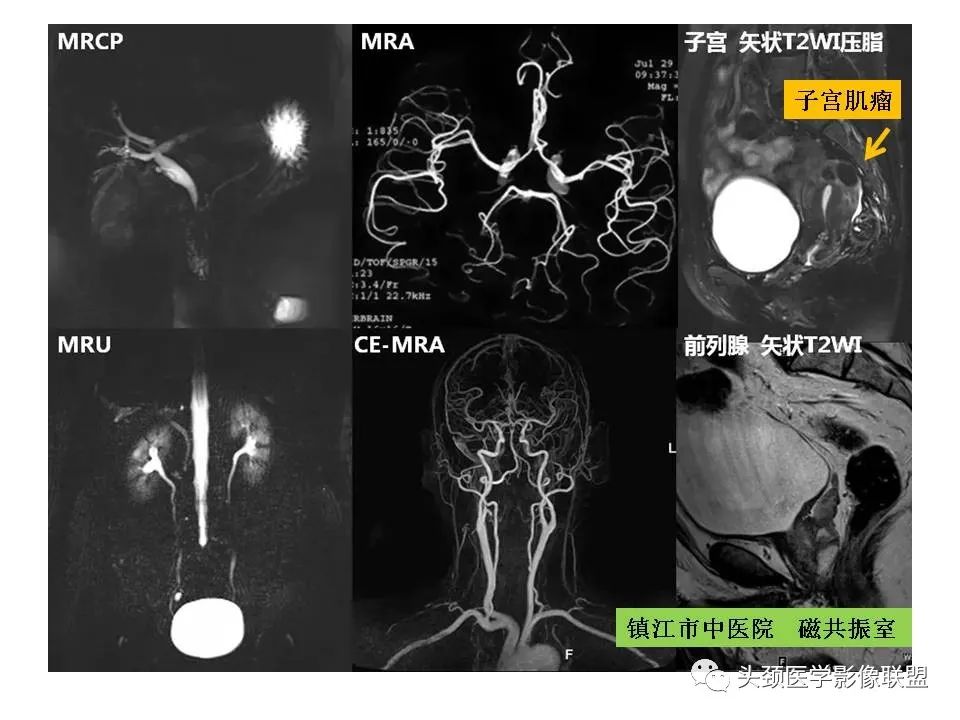

作者:镇江市中医院 谈瑞生

来源:头颈医学影像联盟